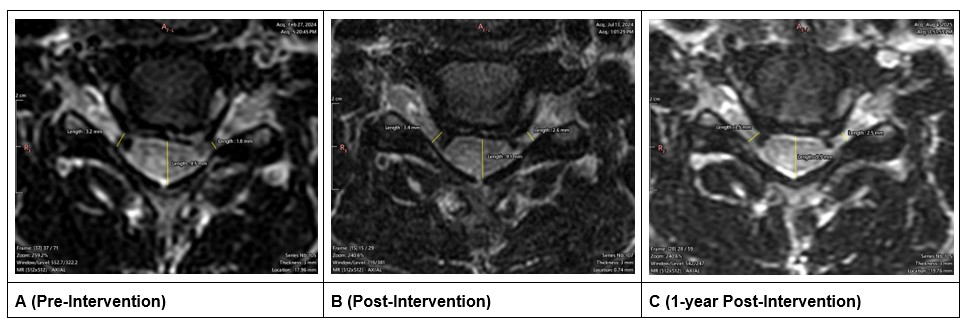

The AP dimension of the spinal canal at C5–C6 level increased from 3.55 mm to 6.70 mm (+3.15mm; 89% increase) after treatment (Figures 4A and 4B). At 1 year the AP dimension decreased by 0.72 mm resulting in an overall increase of 2.43 mm (68% increase; Figures 4A and 4C). The foraminal gap between the vertebrae and the disc at the C5–C6 level increased from 1.79 mm to 2.60 mm (+0.81 mm; 45% increase) on the left side (symptomatic side) and increased from 3.24 mm to 3.43 mm (+0.19 mm; 5% increase) on the right side (Figures 4A and 4B). At 1 year follow up, the foraminal gap on the left side decreased by 0.08 mm resulting in an overall increase of 0.73 mm (41% increase); on the right side, the foraminal gap increased by an additional 0.03 mm resulting in an overall increase of 0.22 mm (7% increase; Figures 4A and 4C).

Figure 4. Axial MRI slices at the C5-C6 level. A is before treatment, B is after treatment, C is 1-year follow-up. These images also show the representative measurements of the left and right foraminal gap at its narrowest point.